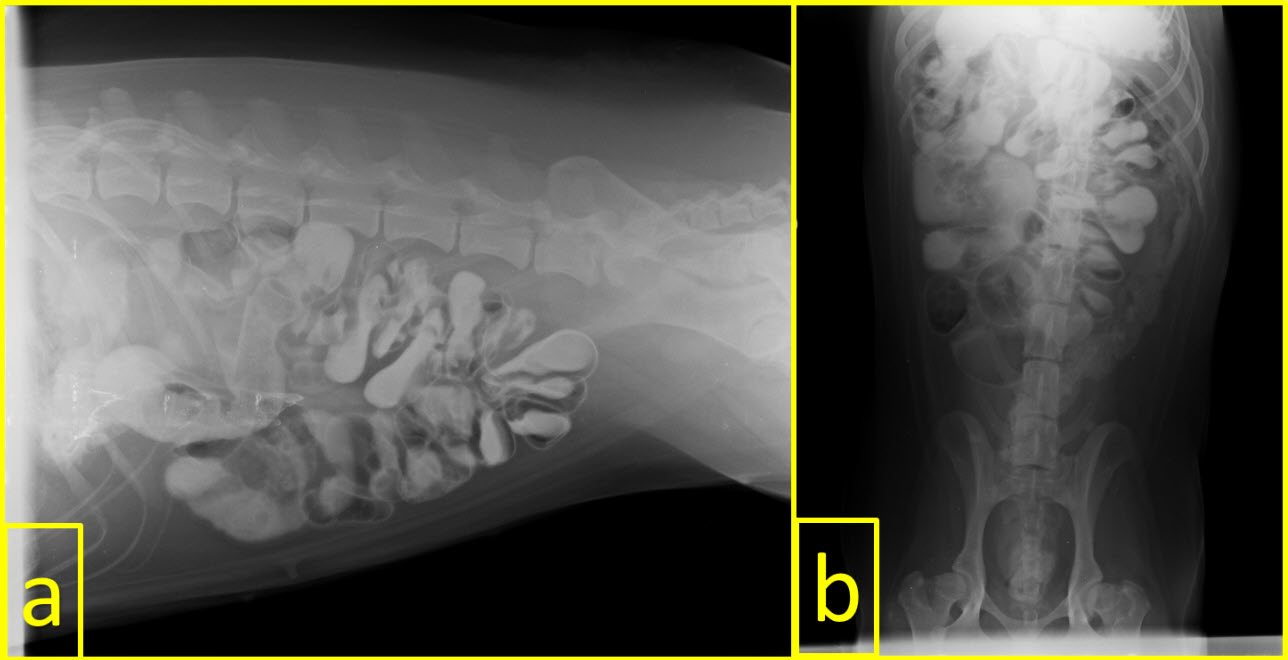

The locations of FB in the gastrointestinal system were as follows: stomach in 14 (43.75 %) animals, small intestine in 10 (31.25 %), esophagus in six (18.75 %), and large intestine in three (9.38 %). FB were detected in both small intestine and large intestines only in one patient. Some of the FB detected by radiography are shown in FIGS 3 and 4.

FIGURE 4. A typical accordion image on indirect radiography due to swallowing of a rope in a dog. a: Latero-Lateral (LL) view and b: Ventro-Dorsal (VD) view